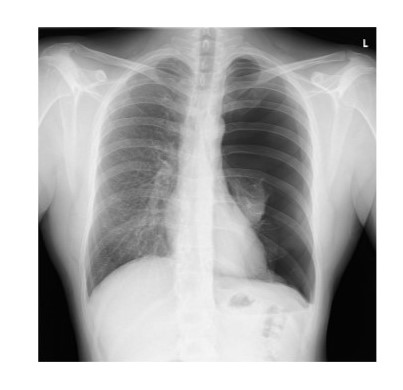

Diagnosis?

knowt flashcard image